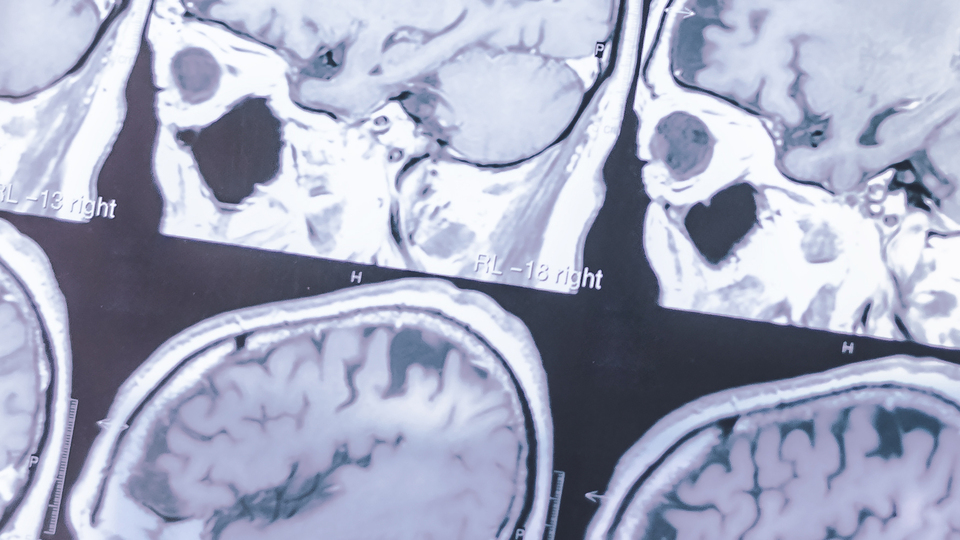

Alzheimer, Parkinson, MS gibi pek çok beyin hastalığı oldukça yaygın olarak görülüyor. Ancak tedaviler oldukça kısıtlı, çünkü beyin diğer organlar kadar iyi anlaşılamıyor. Beyin hastalıklarının anlaşılabilmesi için, spesifik olarak bir hastalıktan sorumlu olan sinir hücrelerini ve hormonları ölçebilmemiz gerekiyor. Yani hücresel olarak beyne ulaşabilmemiz gerekiyor. Ancak biz şu an sadece manyetik rezonans cihazları (MRI) ile beyne kan akışının aktif bölgelerini ve elektroensefalografi (EEG) ile elektriksel aktiviteyi ölçebiliyoruz. Kısacası beyne hala sadece kuşbakışı bakabiliyoruz.